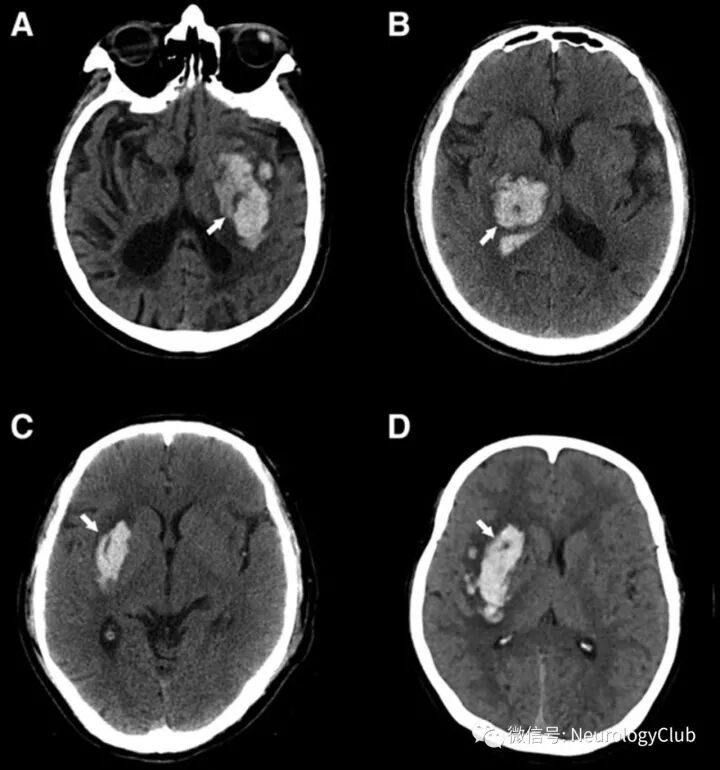

混合征

2015年,李琦等提出CT平扫混合征,并将其定义为同一血肿内混合存在相对低密度区与相邻高密度区的现象,且需满足:(1)低密度区与高密度区之间有明显可被肉眼识别的分界;(2)血肿中2个密度区CT值至少相差18HU;(3)相对低密度区未被高密度区完全包裹。当血液凝固时,血肿在CT上表现为高密度;存在活动性出血时,血肿较血块凝缩更倾向于低密度,不同出血时间的血液混合导致混合征的出现,血肿再次出血进一步导致血肿扩大发生。合征预测ICH患者血肿扩大的敏感性、特异性、阳性及阴性预测值分别为39.3%、95.5%、82.7%和74.1%,比点征具有更高的特异性。首次CT混合征阳性的ICH患者血肿体积明显>阴性者,并且血肿更易扩大,因此混合征可作为血肿扩大的独立预测因素。最近研究发现,脑出血上可见混合征患者预后较差。

(图3:基底节和脑叶出血的混合征)

(图4:脑出血混合征)

黑洞征

2016年,李琦等在ICH患者CT平扫影像中发现黑洞征,将其定义为血肿内黑洞(低密度区)被相邻高密度血肿完全包裹的现象,且需满足:(1)形状各异(可为近圆形或杆状),但与邻近脑组织不相连;(2)有明显的边界;(3)血肿内两密度区的CT值至少相差28HU。黑洞征预测ICH患者早期血肿扩大的敏感性、特异性、阳性预测值及阴性预测值分别为31.9%、94.1%、73.3%及73.2%。血肿的异质性可能反映不同时期的出血,新鲜出血在CT图像中表现为低密度;血液凝固后,血清从中分离,在CT中则表现为高密度。黑洞征的出现表明异质血肿内存在不同时期的出血,因此可作为ICH患者血肿扩大的预测因素。

(图5:脑出血黑洞征